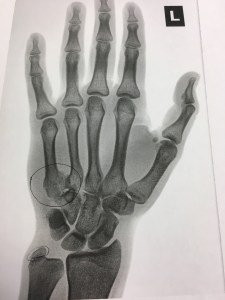

IMG_6144 Published by Kalyn Fan of triathlon, craft beer, and anything outdoors. Supporter of equity and social justice. Health care pro working in Boston. View all posts by Kalyn